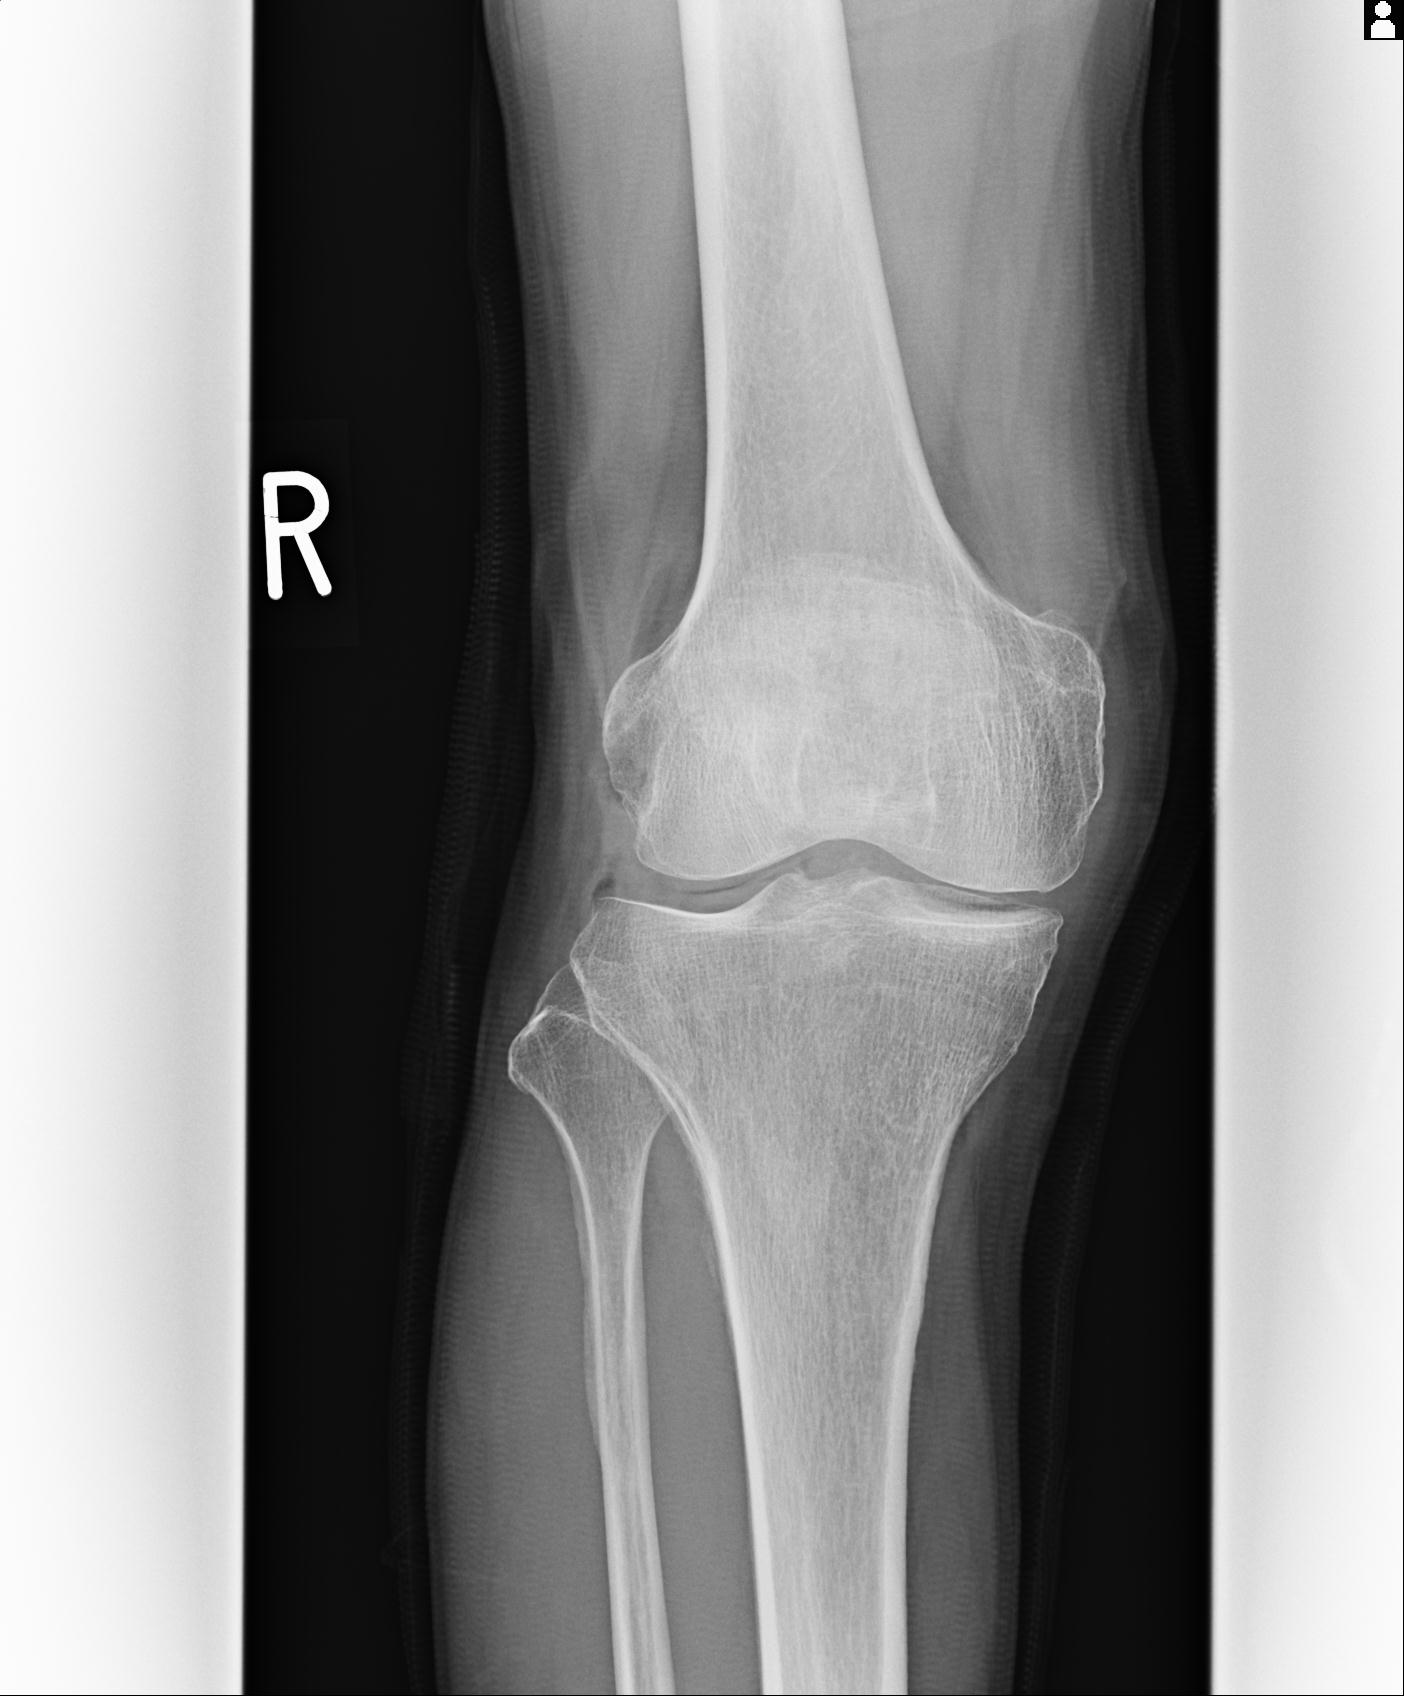

91983 11/16 左膝 2R 11/18 2R 55歳男性 脛骨骨切り術